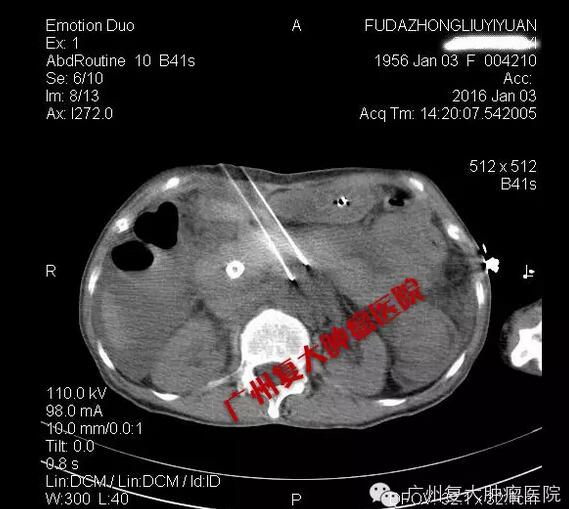

纳米刀消融肿瘤

陈女士的手术很顺利,CT加B超双引导双监测,肿瘤消融达到了90%以上。目前患者已经顺利脱离呼吸机,病情平稳,今天已离开ICU回到普通病房。我们计划几天后开始给予其他的抗肿瘤治疗,包括微血管介入和肿瘤免疫治疗。希望通过我们的努力,能给这位晚期胰腺癌患者更多的生存机会。祝福她!